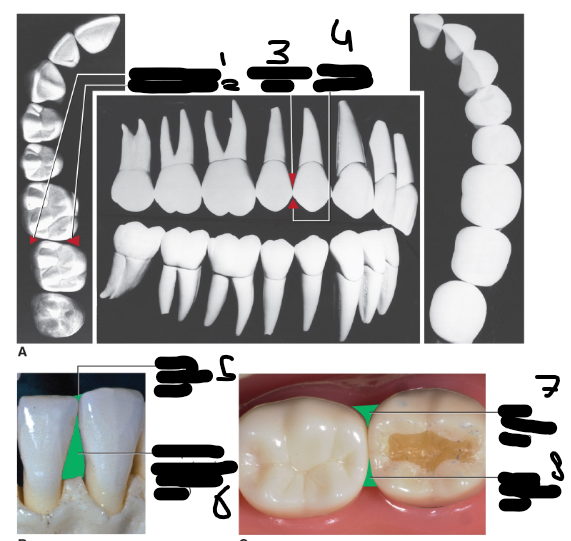

Anatomic root, Anatomische wortel (Afbeelding)

11

Anatomische kroon, Anatomic Crown (Afbeelding)

12

Foramen apicale, Apical foramen (Afbeelding)

1

Wortel kanaal, Root canal (Afbeelding)

2

Cementum (Aflbeelding)

3

Dentine, Dentin (Afbeelding)

4

Cement-dentine grens, Cementodentinal junction (Afbeelding)

5

Pulpa kamer, Pulp chamber (Afbeelding)

6

Glazuur-cementgrens, Cementoenamel junction (Afbeelding)

7

Glazuur, Enamel (Afbeelding)

8

Glazuur-dentinegrens, Dentinoenamel junction (Afbeelding)

9

Linguale oppervlakte van de kroon, Lingual surface of crown (Afbeelding)

10

Glazuur-dentine grens, Dentinoenamel junction (Radiografisch)(Afbeelding)

Glazuur, Enamel (Radiografisch)(Afbeelding)

Dentine, Dentin (Radiografisch)

Pulpa, Pulp (Radiografisch)(Afbeelding)

Ligamentum parodontale, Periodontal ligament (Radiografisch)(Afbeelding)

5 (Donkere lijn)

Alveolair bot, Alveolar bone (Radiografisch)(Afbeelding)